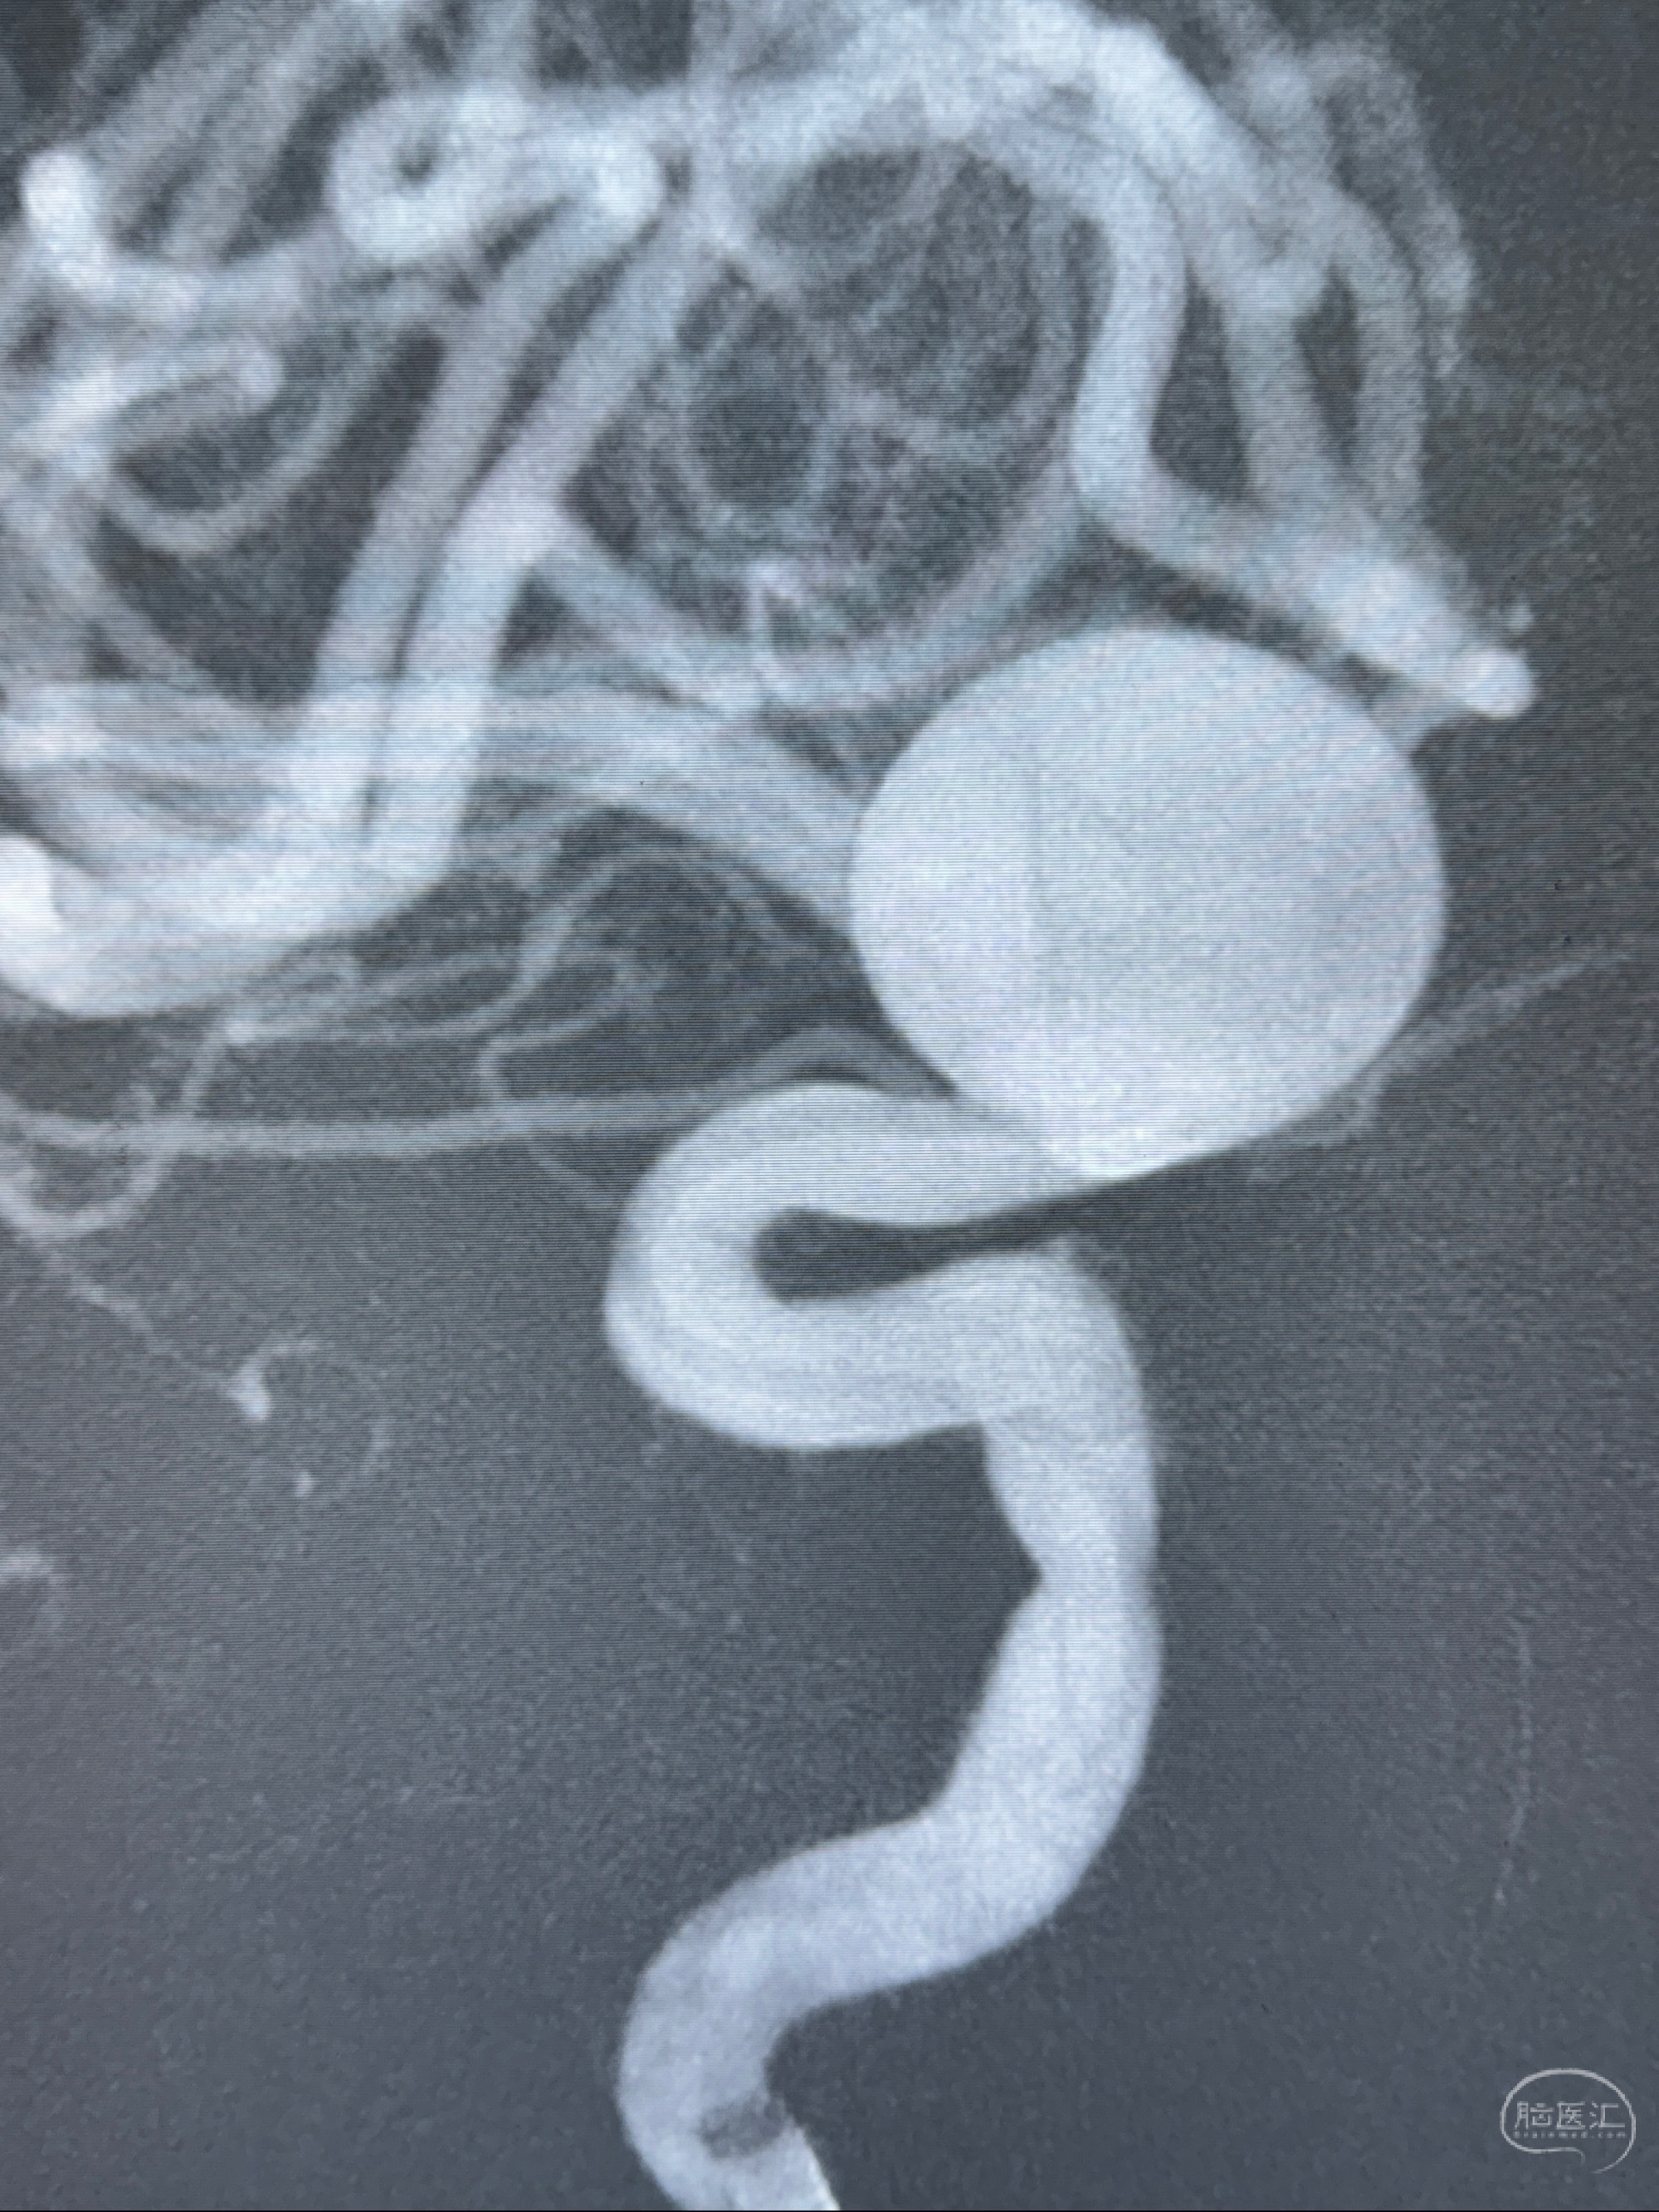

2023-12-08 复旦大学附属华山医院 全脑血管造影:右侧颈内动脉C6段动脉瘤,瘤颈6.68mm,动脉瘤大小13.28*12.34mm

2023-12-08外院DSA:右侧颈眼动脉瘤,约13*12mm大小,压颈试验显示左右向及后向前代偿可

测量动脉瘤的大小:16*13.8*7.6mm大小,较原先变大,考虑双抗后瘤内血栓溶解可能